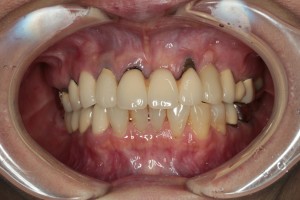

症例⑤

上左右の奥歯を失ってしまったため、保険の入れ歯を入れたが、違和感が強く、しっかり噛むことができないため、インプラントを併用した入れ歯を作ることで違和感なく、しっかり噛むことができるようになった。 また通常の入れ歯は、はずれないようにするため金属のバネを歯に引っ掛けるため見た目も悪いが、インプラントによって固定されているためバネもなく、見た目も非常に良いものとなっている。

術後レントゲン写真